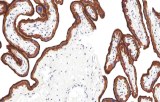

La tiroglobulina se utiliza ampliamente como marcador de epitelio folicular tiroideo diferenciado y es útil para respaldar el origen tiroideo tanto en lesiones primarias como metastásicas. La expresión puede estar reducida, focal o ausente en carcinomas tiroideos poco diferenciados o desdiferenciados; la interpretación debe considerar posibles limitaciones técnicas y contextuales.

PAX8 es un factor de transcripción nuclear expresado en células foliculares tiroideas y es útil para respaldar el linaje tiroideo, particularmente en tumores con expresión disminuida o ausente de tiroglobulina. La interpretación requiere conciencia de que la expresión de PAX8 no es específica del tejido tiroideo y puede observarse en neoplasias epiteliales no tiroideas seleccionadas.

La calcitonina es el marcador inmunohistoquímico principal de diferenciación de células C parafoliculares y es central para el diagnóstico de carcinoma medular de tiroides en la mayoría de los casos. Aunque muestra alta utilidad diagnóstica en entornos primarios y metastásicos típicos, se han reportado tumores calcitonina-negativos raros; los resultados deben interpretarse junto con morfología, hallazgos clínicos y estudios complementarios cuando esté indicado.

La galectina-3 es uno de los marcadores inmunohistoquímicos más estudiados en patología tiroidea y se expresa con mayor frecuencia en tumores malignos derivados de folículos que en nódulos benignos. Sin embargo, también puede observarse expresión en ciertas condiciones tiroideas benignas o inflamatorias. Por lo tanto, su valor diagnóstico es mayor cuando se utiliza como parte de un panel inmunohistoquímico multiparamétrico en lugar de como marcador independiente.

La hormona paratiroidea es un marcador clave para confirmar el origen paratiroideo y es particularmente útil en el diagnóstico diferencial entre lesiones paratiroideas y tiroideas con características histológicas superpuestas. Apoya la confirmación de linaje en adenomas paratiroideos, carcinomas y tejido paratiroideo ectópico o intratiroideo; la interpretación se realiza en correlación con morfología y hallazgos clínicos.